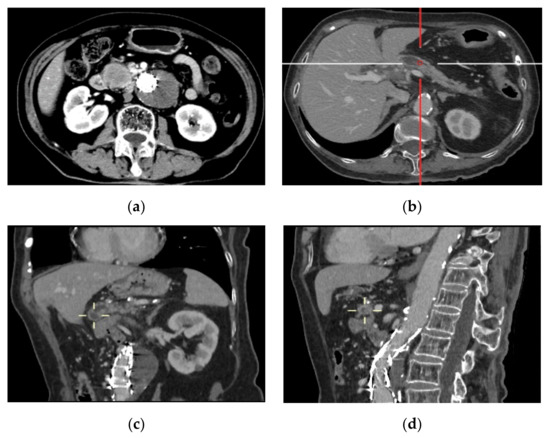

Presentation of Case